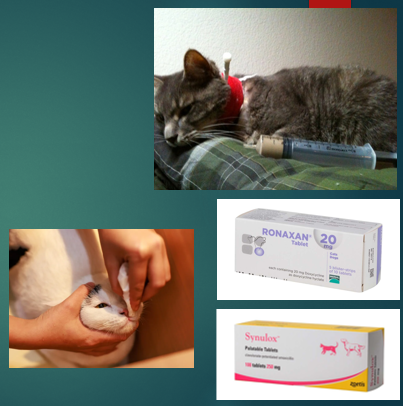

Treatment of cat flu

Isolated - infectious

Antibiotics → Bordetella bronchiseptica, Chlamydophila, Secondary infections

Anti-viral medication

Fluid therapy

nutrition

Mucolytics

Nursing care - grooming is very important in these cases, cleaning the face and eyes regularly to get rid on the mucous is really important

Mucolytics

Helps to break down discharge